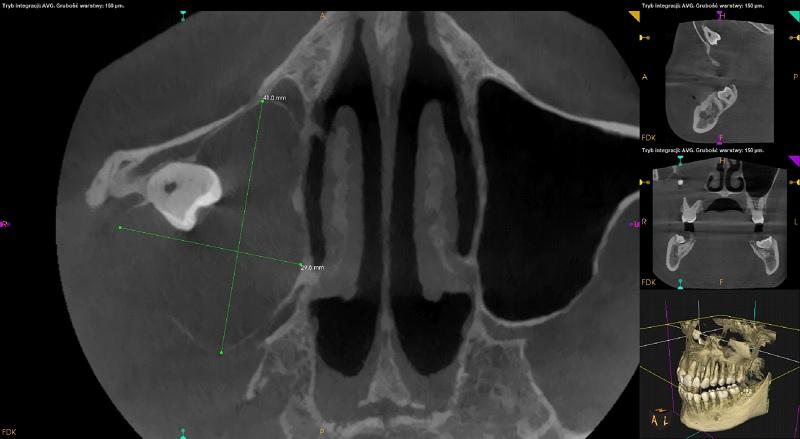

Rozległa zmiana w widocznym zakresie prawej zatoki szczękowej modelujące, uwypuklające, cienkie ograniczenia kostne zatoki z rozległą destrukcją bocznej ściany oraz dna zatoki w okolicy 18 (około 41mm x 29,5mm x 38,5mm). Rozdęcie zarysu wyrostka zębodołowego w okolicy 16-17 z destrukcja blaszek zbitych po stronie przedsionkowej i podniebiennej. Wierzchołki korzeni zębów 17,16 objęte zmianą – widoczna resorpcja wierzchołków korzeni. Zmiana wpukla się do przewodu nosowego środkowego prawego ograniczając jego drożność. Przemieszczony ząb 18 widoczny w części górnej zatoki przy ścianie przedniej. Możliwa torbiel zapalna, mucocele - do pilnej konsultacji laryngologicznej i chirurgicznej z ewentualnym poszerzeniem diagnostyki (np. w badaniu TK z kontrastem iv), ocena kliniczna i ew.biopsja.